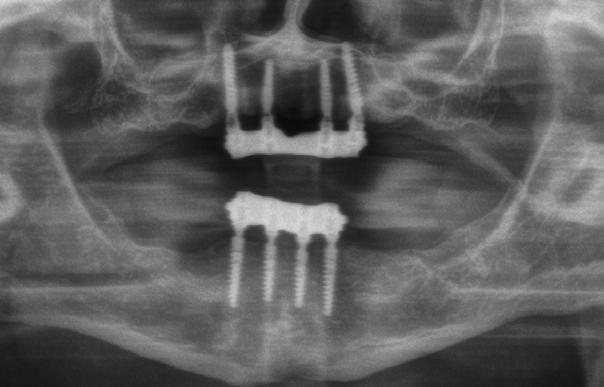

Az 50 éves nőpáciens az alsó és felső állcsont területén egyaránt panaszt (fájdalom, ráharapási érzékenység) okozó, harmadfokban mozgatható fogak miatt jelentkezett rendelőnkben. Az általános anamnézisben említést érdemlő betegség, műtét nem szerepelt. Az elvégzett klinikai és radiológiai vizsgálatok (1–2. ábra) alapján fogai reménytelen parodontális státusúnak bizonyultak, hosszú távon sem megtartásuk, sem protetikai célú felhasználásuk nem volt lehetséges. A parodontális prognózis a fogak eltávolításának abszolút indikációját jelentette. Ezáltal mindkét állcsontban teljes foghiány kialakulásával kellett számolnunk. A protetikai szemléletű, „visszafelé” tervezés elveit követtük a hosszú távú funkcionális, esztétikai siker és szöveti stabilitás elérése érdekében: mindkét állcsontban overdenture típusú fogpótlás készítése mellett döntöttünk. A megfelelő implant-protetikai rehabilitáció alapja az implantátumok megfelelő pozicionálása. A korábbi parodontális kórfolyamat következtében a processus alveolarisokat érintő eredendő csontdeficittel kellett számolnunk, amelyet tovább súlyosbíthatott volna a hagyományos extrakciós technikát követő involúciós atrófia. Ezért a páciens kivizsgálása és megfelelő előkészítése után a fog eltávolításával egy időben PRF

A fogak eltávolítása és az alveoláris csont megőrzésének és regenerációjának segítése céljából elvégzett augmentáció altatásban történt. Óvatos, atraumatikus extrakciót követően eltávolítottuk a parodontális és periapikális gyulladásos folyamatok eredményeként jelen lévő sarjszövetet. A bukkális csontfal hiánya és a tervezett vertikális augmentáció miatt indokolt membrántechnika megfelelő kivitelezése céljából a felső állcsonton mukoperioszteális lebenyt képeztünk (3–4. ábra). Az alveolus prezervációt Sticky Tooth, PRF és titánerősítésű teflon (PTFE-Ti) membránok segítségével végeztük el, a J. Choukroun által megadott vérvételi és centrifugálási protokoll (28) elveinek betartásával: kizárólag Process for PRF Duo Quattro System eszközöket, centrifugát, vérvételi egységet és csöveket, a membránok előállításához PRF Boxot használtunk. Az A-PRF és S-PRF csöveket a PomPac eljárásnak megfelelően 4 Celsius-fokra előhűtöttük. Az eltávolított fogak makroszkópos tisztítását és darabolását nagy fordulattal (300 000 RPM) fogászati turbinába helyezett gyémántfúróval végeztük, majd Tooth Transformer™ berendezéssel, annak gyári reagens rendszerével kezelt őrleményt nyertünk. A Sticky Tooth készítmény előállítása a PRF készítmény és az őrlemény

60/40 arányú keverésével történt (5–7. ábra), A-PRF és A-PRF/S-PRF membránokat készítettünk (8. ábra). Az alveólusokat a grafttal feltöltöttük, a felső front régióban vertikális augmentációt végeztünk a tervezett alveoláris csontmagasság elérésének céljából (9–10. ábra). A vertikális augmentáció támogatására titán mikrocsavarokkal rögzített, titánerősítésű teflonmembránokat alkalmaztunk, amelyekre egy rétegben A-PRF membránokat, és egy rétegben A-PRF/S-PRF membránokat helyeztünk. Az alsó állcsont esetében vertikális augmentáció nem volt szükséges, célunk az alveoláris kemény- és lágyszöveti struktúrák prezervációja volt, a graftot csak PRF memb-

A gyógyulási időszakot követően a csontos gyógyulás ellenőrzése és az implantáció tervezése céljából állcsonti CT-felvételt készítettünk. A CT-felvételen tökéletes csontos gyógyulást észleltünk, az alveoláris csont volumene

teljes mértékben megtartott, a vertikális augmentáció a tervezettnek megfelelő eredményű volt (13–15. ábra), a klinikai kép is ennek megfelelően alakult, optimális menynyiségű keratinizált ínnyel és azt adekvát sebészi technika eredményeképpen megtartott vesztibulummal (16–17. ábra). Az alsó és felső állcsontba 4-4 darab Bredent COPA Sky implantátumot ültettük, D1-D2 csontminőség mellett,